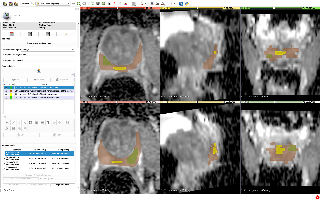

StructSeg2019

| 名称 | 标注内容 | 类型 | 模态 | 数量 | 标签格式 | 文件格式 |

|---|---|---|---|---|---|---|

| StructSeg2019 |